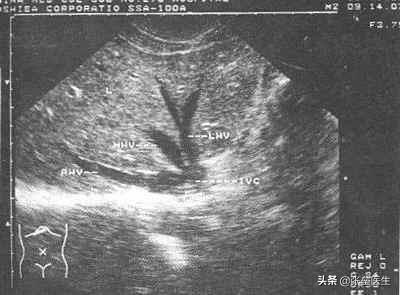

4番目だ。肝臓超音波検査超音波検査は "レーダー "のようなもので、肝臓の形状に異常がないか、肝臓の損傷の程度はどうか、実質的な病変(脂肪肝、肝硬変など)はないかなどを超音波画像で診断することができる。

(1) 肝臓の超音波検査

- まず最も重要なのが肝臓の超音波検査で、日常生活で最もよく利用される検診でもあり、特に低コストで認知度が高いという利点から費用対効果に優れていると広く評価されている。肝臓の超音波検査では、肝血管腫、肝嚢胞、脂肪肝などの病気をはっきりと見つけることができ、画像から病期や重症度を判断することもできます。また、肝臓の超音波検査は、胆嚢結石、肝内胆管結石、総胆管結石をより正確かつ高感度に検出できるという利点があります。

- 私は、45歳以下の健康な人は毎年肝臓の超音波検査を受けることを勧めています。いつ受けるかはあなた次第ですが、検査の前に食事をするのはやめましょう!また、年に2回の検査が可能かという質問もあります。もし経済的に年2回の肝臓超音波検査が可能であれば、それは素晴らしいことで、検査期間を短縮すれば、肝臓の病変を早期に発見でき、病気の早期発見、早期治療につながります。

- 加えて肝臓の超音波検査は体にも無害で、頻繁に検査しても放射線などの危険はない。

2.B超

肝臓を調べるのに最も費用対効果が高く便利な検査は、超音波検査である。脂肪肝でも、肝嚢胞でも、肝血管腫でも、肝膿瘍でも、肝内胆管結石でも、肝硬変でも、肝臓がんでも、すべて見ることができます。

肝臓の超音波検査は、現在では基本的に病院の検診項目に含まれている。肝嚢胞、肝血管腫、脂肪肝が最も一般的な診断です。脂肪肝は大きな問題ではありませんが、肝機能の変化を引き起こす場合は治療が必要です。肝嚢胞は通常5cm以上の大きさで、治療が必要な症状があります。もちろん、症状のない10cm以上の肝嚢胞も治療が必要です。肝血管腫も良性疾患であり、治療基準は肝嚢胞と同様で、大きさや症状によって異なります。

超音波検査は、肝臓の臨床画像診断で最もよく用いられる方法で、肝臓の形態異常の有無、肝硬変の有無と程度、肝臓の脂肪沈着や空間占拠性病変の有無、肝内・肝外胆道系の異常の有無、肝血行動態の異常の有無、胆嚢機能の正常の有無などを判断することができる。一般的に、熟練した超音波検査技師であれば、5mm以上の大きさの病変を検出することができる。もちろん、経済的に可能であれば、CTやMRIも可能である。

2.肝臓の超音波検査

現在、肝臓超音波検査は、脂肪肝かどうか、肝臓が破裂しているかどうか、もちろん肝臓が成長すべきでないものを成長させているかどうかを調べることができる。

3.イメージング

最も一般的に行われているスクリーニング検査は超音波検査で、超音波とコンピューター画像を使って、肝臓の形態に異常がないか、肝臓の損傷の程度、実質的な変化がないかなどを調べます。肝炎、肝硬変、脂肪肝、肝臓がんなどの病変を初期診断することができます。一般的な健康診断では、肝臓超音波検査で目的を果たすことができ、疑わしい所見や陽性所見がある場合には、さらにCTやMRIを行うことができる。

肝臓の超音波検査

1.検査内容Bモード超音波検査では、肝臓の輪郭、胸壁、腹壁、実質のエコー、管状構造と肝実質の経過、肝静脈と門脈、肝内胆管と肝動脈を観察することができる。

2.検査の目的Bモード超音波画像から変換された検査報告書の様々なデータから、医師は肝臓が正常かどうか、あるいは肝臓疾患があるかどうかを判断することができる。

⑥肝臓超音波検査:この検査は高価ではなく、放射線や外傷がなく、肝臓の血管とその分布、血流、動脈と静脈の内径、肝臓の大きさ、エコー、胆管が拡張していない、腹膜の状態、嚢胞がない、職業がない、脂肪肝がない、肝硬変は非常に直感的な検査することができます一般的な理解を得ることができます。